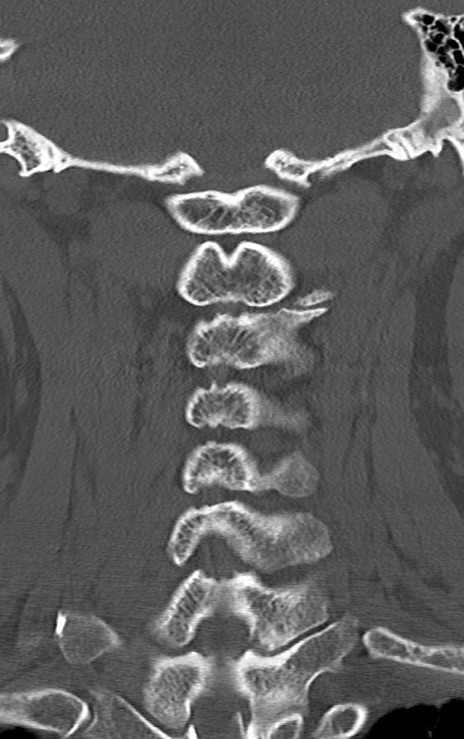

頚椎CT

横断像